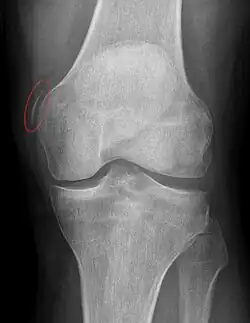

Pellegrini-Stieda Syndrome, image marking of ossification.

The Radiographic Image is shows calcification circled in red.